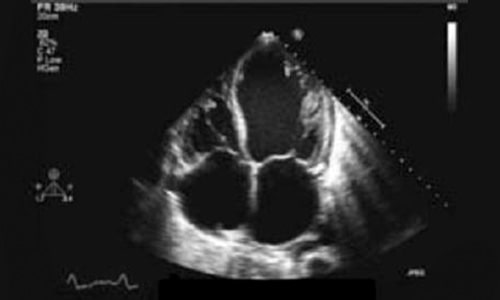

Sou médica formada em 2015 pela Universidade de Ribeirão Preto. Fiz residência de Clínica Médica no Hospital do Servidor Público Estadual de São Paulo e em seguida fiz residência de Cardiologia no Instituto Dante Pazzanese de Cardiologia. Após me especializar como cardiologista optei por me aprofundar em imagem cardiovascular e fiz residência médica em Ecocardiografia também no Instituto Dante Pazzanese, o que me trouxe uma visão muito mais ampla e completa para o domínio e acompanhamento das doenças cardíacas.